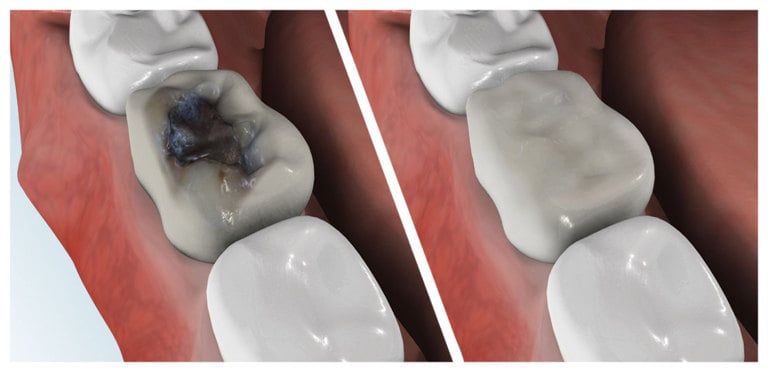

Composite fillings are today's modern filling choice. They are made to match your tooth's natural color to make them virtually invisible to notice and are placed onto the tooth by bonding the filling material to the tooth so they do not have the unlikely chance of falling off. Many patients choose to replace their old silver and gold fillings with composite fillings.

Strong and Natural Looking

White fillings are made from a high-strength composite resin that can be easily color-matched to your natural tooth making it nearly invisible to you and anyone else. Unlike silver and gold fillings, composite tooth-colored fillings actually bond to the tooth which means they support the surrounding tooth structure, which helps to prevent breakage and insulate the tooth from excessive temperature changes. You are much less likely to have a composite filling fall out which is a common issue with metal fillings.